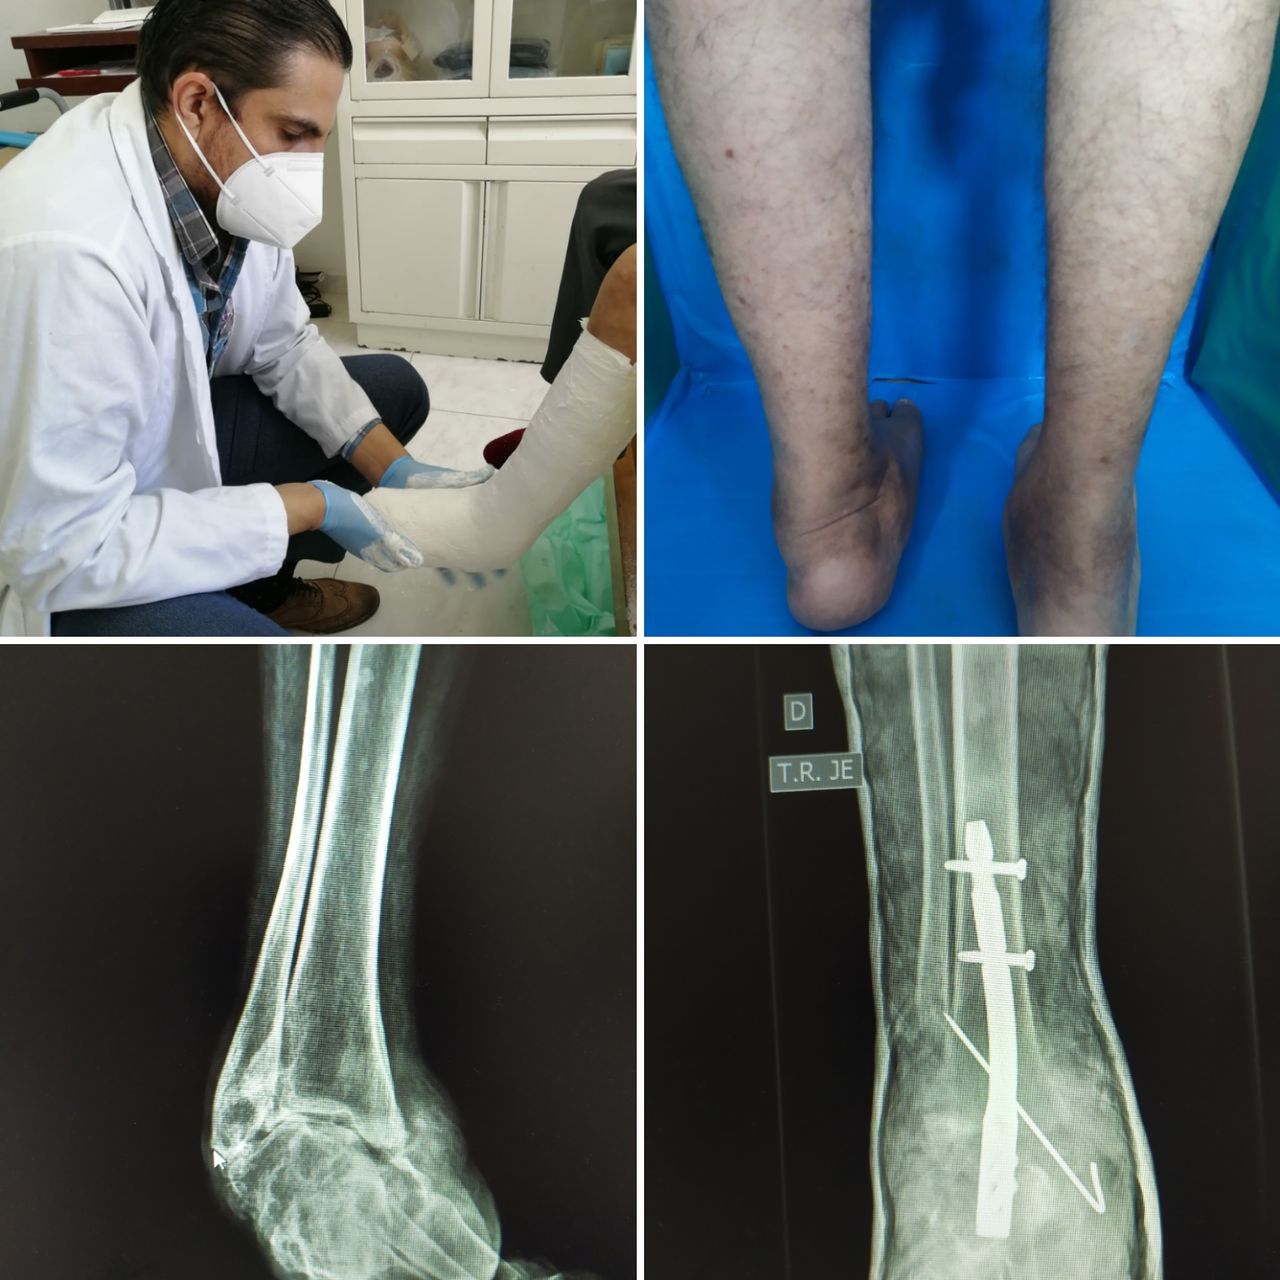

Dr. Rodolfo Ramírez Carrillo

Traumatólogo, Ortopedista

Querido paciente, soy Traumatólogo y Ortopedista egresado del Hospital Central de la Universidad Autónoma de San Luis Potosí, donde me especialicé a tratar todo tipo de problemas en el sistema musculoesqueletico, desgaste, fracturas, luxaciones, lesiones ligamentarias de (hombro, codo, mano, muñeca, columna, cadera, rodilla, pie y tobillo)

Posteriormente hice una Alta Especialidad en el Hospital de la Cruz Roja Mexicana de Mérida Yucatán, donde aprendí a tratar patología específica y compleja de pie y tobillo ( desgaste de tobillo, espolón Calcaneo y Fascitis plantar, Hallux Valgus (Juanetes), Pie plano del niño y del adulto, pie cavo, deformidades de los dedos menores del pie, pie diabético, artropatía de charcot, lesiones del tendón de Aquiles, lesiones deportivas.

• Cirugía de Tobillo

• Cirugía del Pie